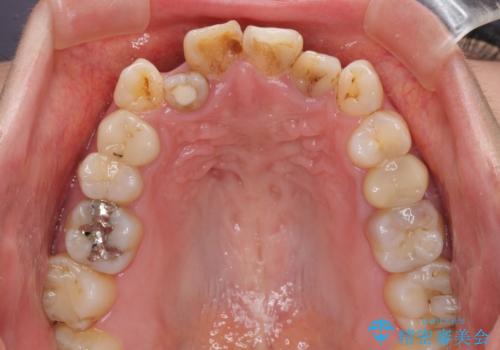

- 八重歯と前歯のデコボコ、開咬を気にして来院された患者様です。

抜歯矯正が必要であることはご自身で理解されており、目立たない装置をご希望であったので、上顎が裏側装置であるハーフリンガル装置にて治療を行うこととしました。

上顎前歯や下顎大臼歯に根管治療の必要な歯がいくつかあるため、矯正治療と並行して根管治療を行い、その後オールセラミッククラウンにて補綴治療を行うこととしました。